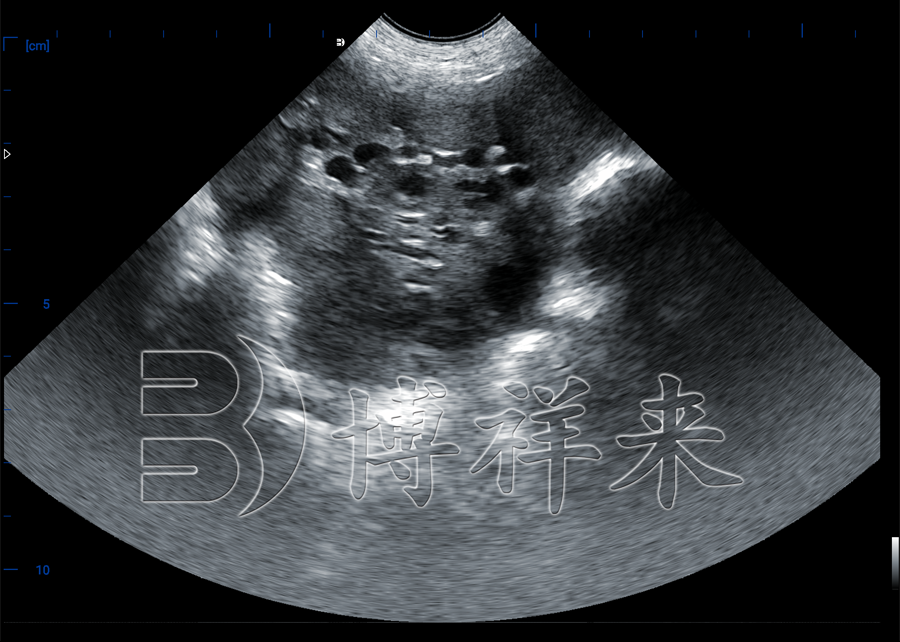

猪卵泡超声影像

猪用B超机是一种专业兽用超声设备,采用B-mode(二维)超声技术,配合高频探头(如3.5 MHz、5 MHz或7.5 MHz),主要用于监测母猪卵泡发育、估测排卵时间、早孕检测及子宫健康评估。

2、操作流程:略去毛发、涂耦合剂 → 探头放置于腹侧乳头后部 → 扫描观测卵泡图像 → 冻结测量直径。

3、专业解读

• 卵泡 < 5mm → 小卵泡期;

• 7–9mm → 排卵前期成熟;

• 10mm → 接近排卵状态。